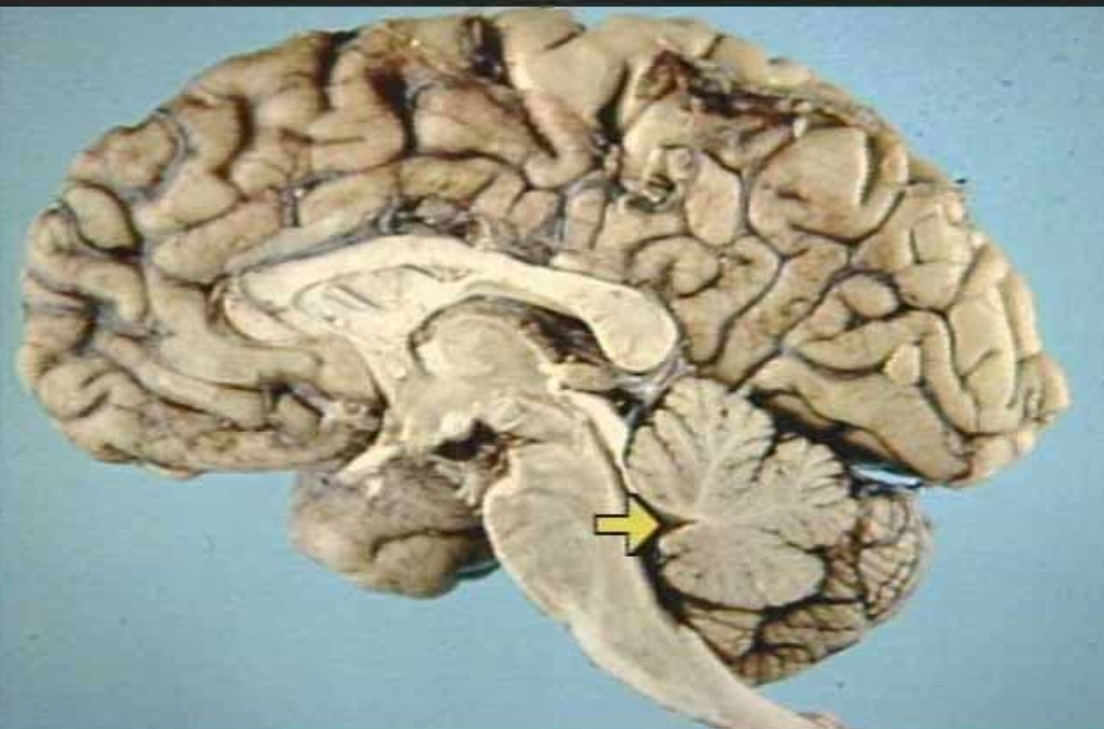

What is the arrow pointing at?

Fourth Ventricle (arrow)